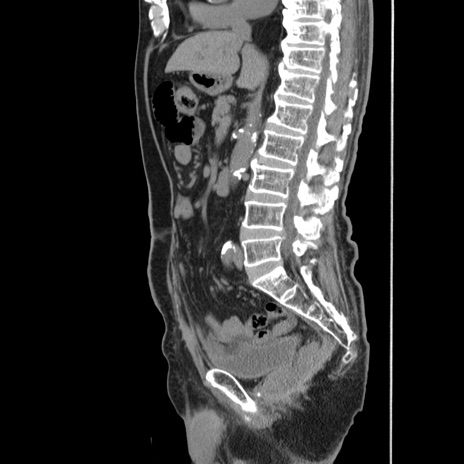

症例24(矢状断像)

【症例】80歳代男性

【既往歴】直腸癌(Mile手術)、胆摘

【身体所見】意識清明、BT 35.9℃、BP 221/93mmHg、SpO2 97%(RA) 、腹部:左ストーマ周囲に限局性の腹部膨隆あり。 膨隆部自発痛・圧痛あり・軟。

横断像